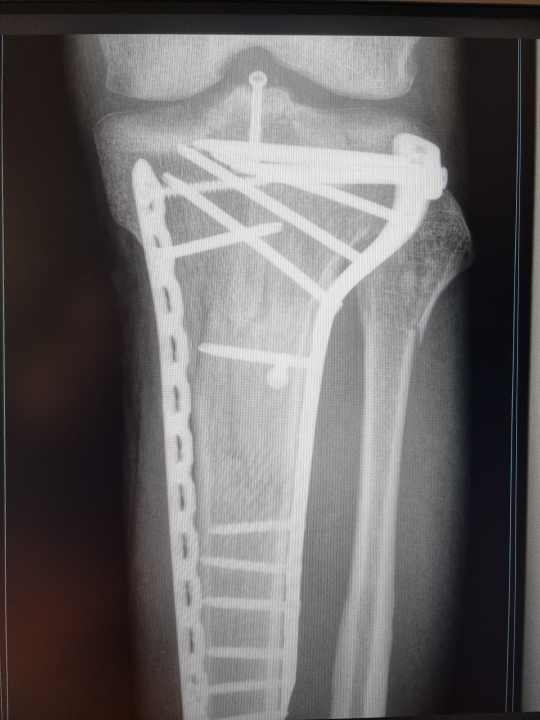

Nachdem mich ein Sturz mit einem zertrümmerten Schienbeinkopf und ohne funktionstüchtigem vorderen Kreuzband zurückließ, habe ich ein hohes Risiko für weitere Knie-Probleme. Über die Jahre gaben mir Ärzte und Therapeuten ganz unterschiedliche Tipps. Es scheint, als sage jeder etwas anderes zum Thema Mountainbiken als Knie-Patient. Die Belastungen beim Biken sind ziemlich komplex. Einen wirklichen Experten zu finden ist gar nicht so einfach. - Jan Timmermann, BIKE-Redakteur

Verletzungen durch Stürze sind geschwindigkeitsabhängig und können zum Beispiel auch komplexe Knochenfrakturen sein. Ein weiteres Problem beim Sturz aufs Knie ist das Gewicht. Auffällig ist seit der Verbreitung von E-MTBs die Zunahme an Tibiakopf-Frakturen (Bruch des Schienbeinkopfes, Anm. d. Redaktion). Diese sind für das Kniegelenk relativ heftig, weil sie oft mit einer Verletzung von Bändern und Kapseln in Verbindung stehen. Bei einem schwereren Bike kommt es natürlich zu höheren Kräften. Bezieht man das meist höhere Tempo von E-Bikes mit ein, steigt die Belastung exponentiell.

Prinzipiell sollte es im Reha-Prozess das Ziel sein so viel, wie möglich an Beweglichkeit wiederzuerlangen. Bei einer schweren Verletzung, wie einer Tibiakopf-Fraktur ist das nicht immer einfach. Das ist kein angefahrener Kotflügel mehr, sondern eine starke Beeinträchtigung der statischen Situation und der Gelenkmechanik im Knie. Wer eine Verletzung hat, sollte unbedingt versuchen den Bewegungsbereich des Gelenks so lange wie möglich zu erhalten. Bei einem Streckdefizit von fünf Grad beispielsweise darf sich dieses nicht schleichend auf zehn oder sogar 15 Grad erhöhen. Der Körper reagiert dann nämlich mit Ausgleichsbewegungen in der Hüfte oder im Becken und Bewegungsabläufe werden nicht mehr funktionell sauber ausgeführt, was dann Probleme in anderen Körperpartien indiziert.